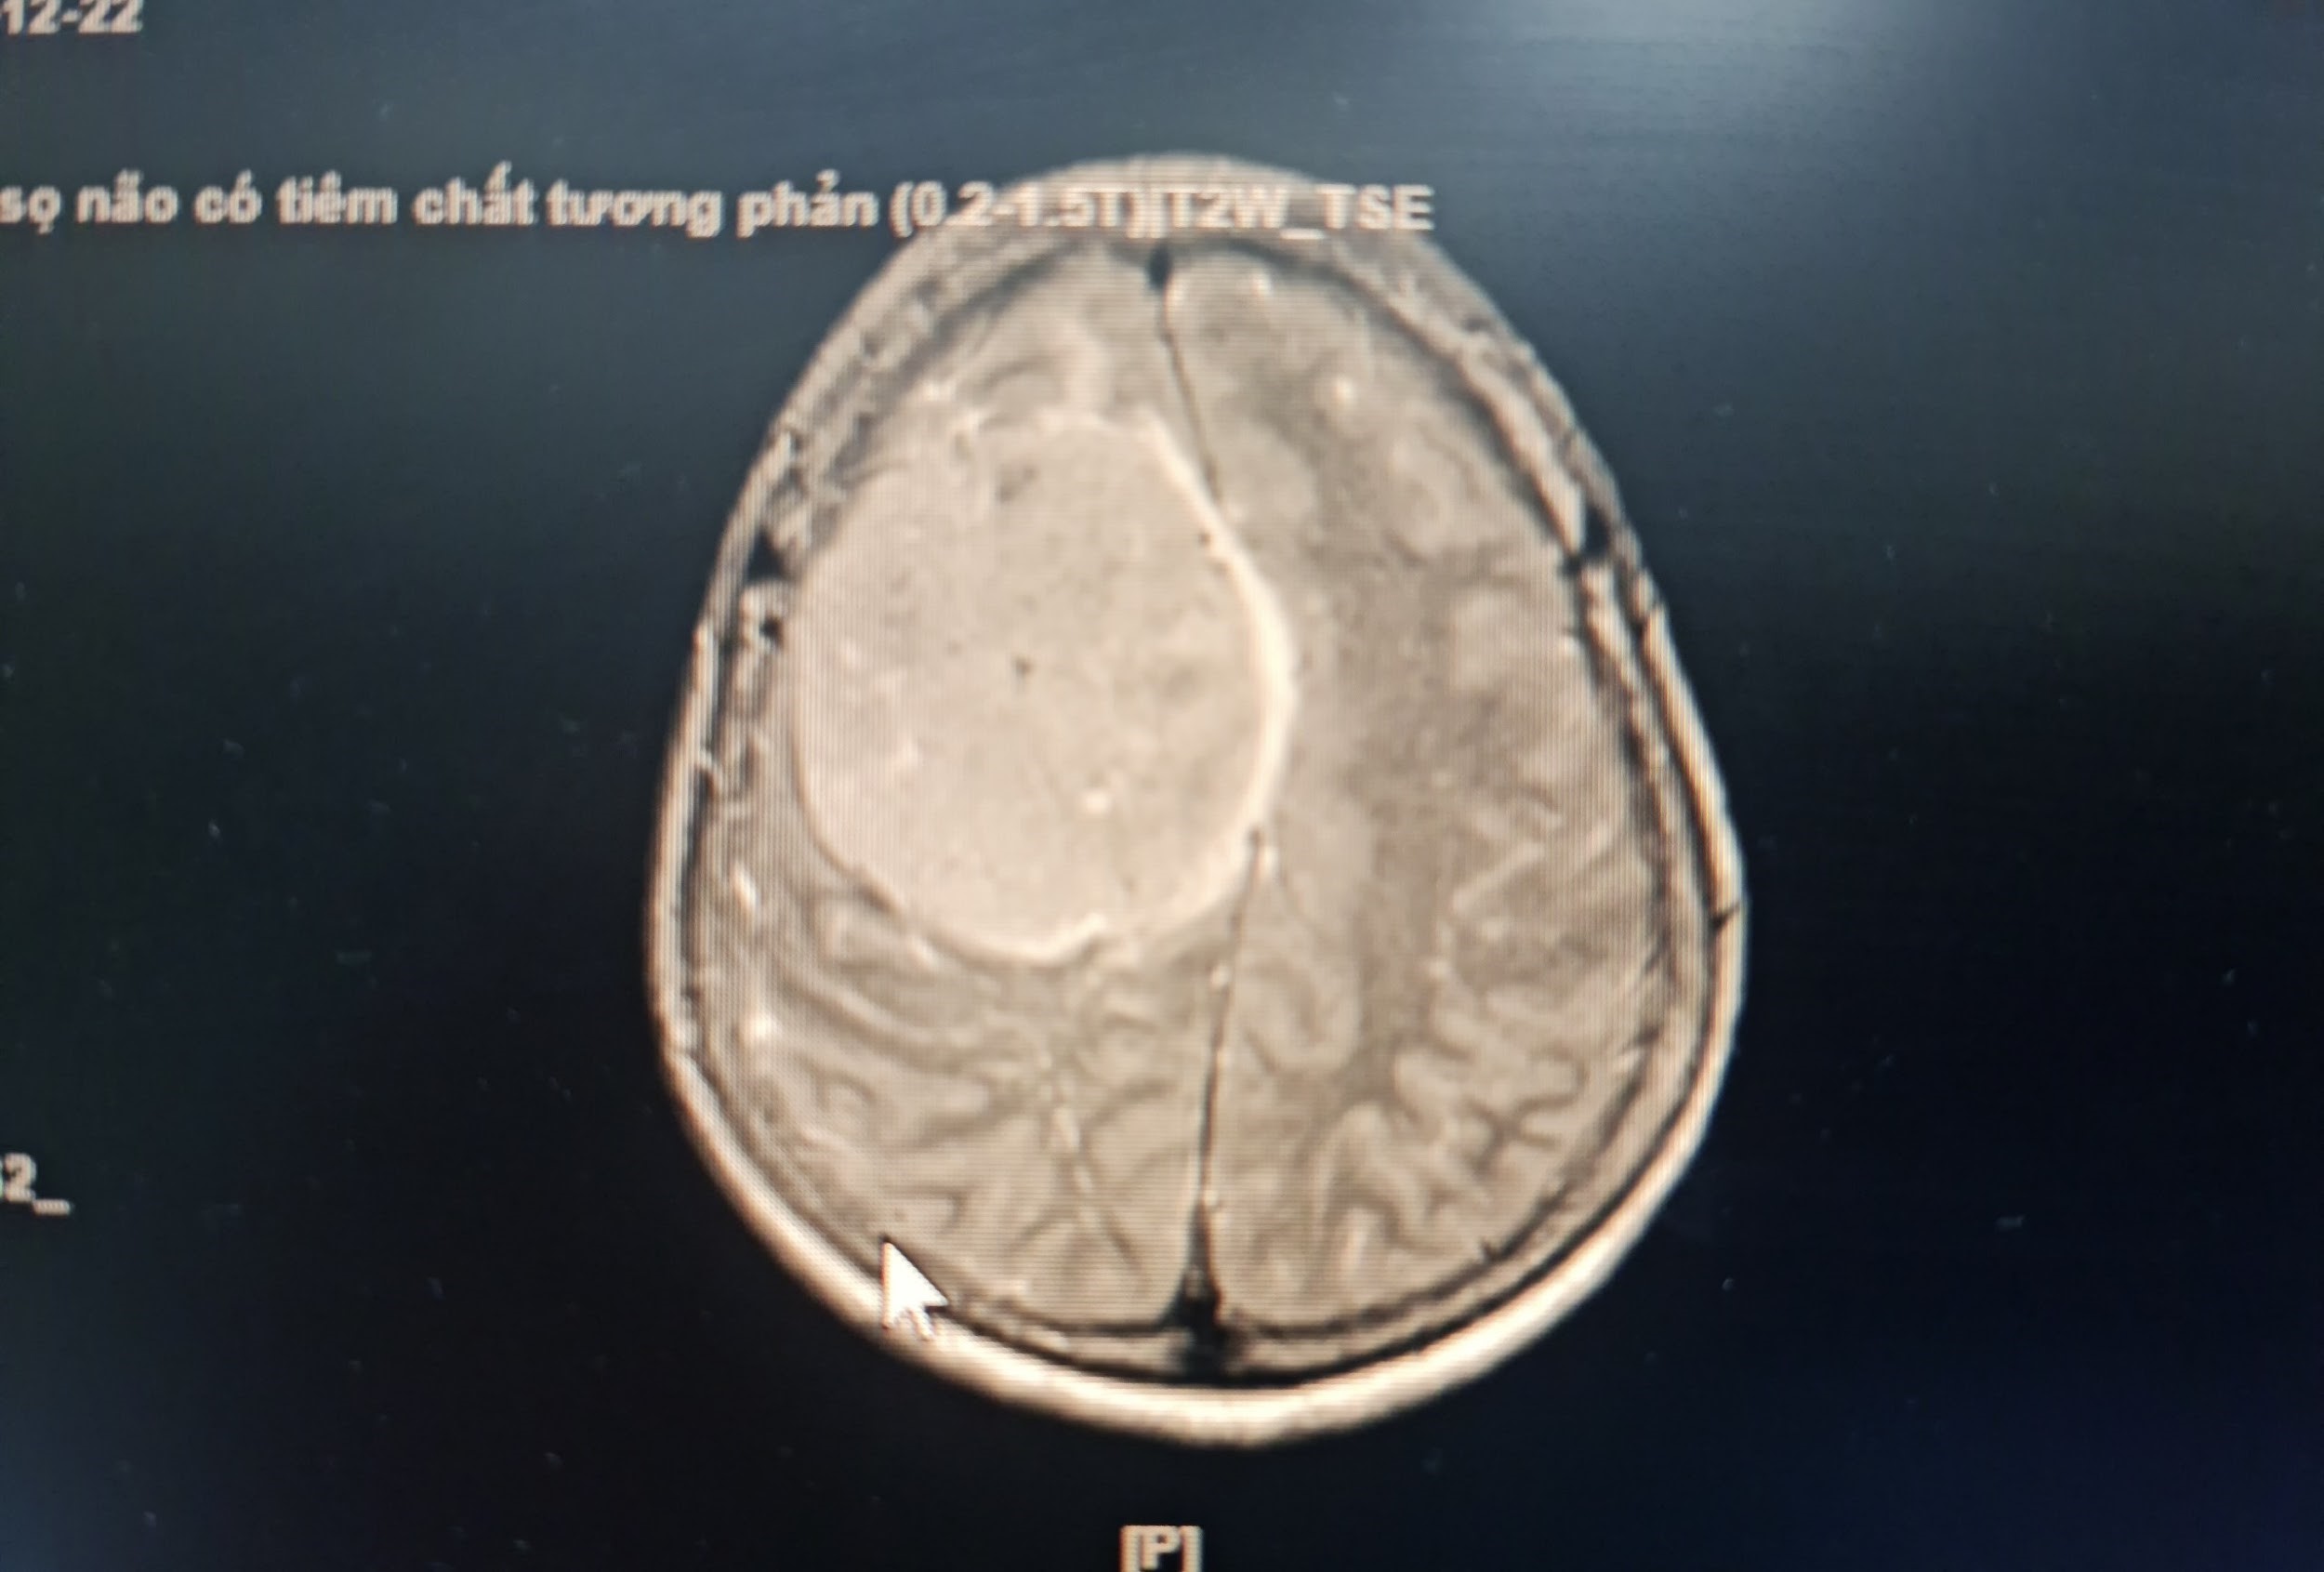

Kết quả thăm khám và chụp MRI sọ não có tiêm thuốc tương phản tại Bệnh viện Đa khoa tỉnh Thanh Hoá phát hiện bệnh nhân có khối u màng não bán cầu phải, kích thước lớn 7x8cm. Khối u nằm sát, xâm lấn xoang tĩnh mạch dọc giữa và 1 phần xương sọ, gây chèn ép ¼ não và phù não xung quanh. Bệnh nhân và người nhà được các bác sĩ tư vấn cần sớm phẫu thuật điều trị, vì khối u lớn sẽ chèn ép, gây nhiều tổn thương nghiêm trọng đến nhiều chức năng của cơ thể bệnh nhân như: vận động, thị giác, nhận thức,… và thậm chí có thể tử vong.

Hình ảnh khối u của bệnh nhân trên phim chụp MRI sọ não tiêm chất tương phản